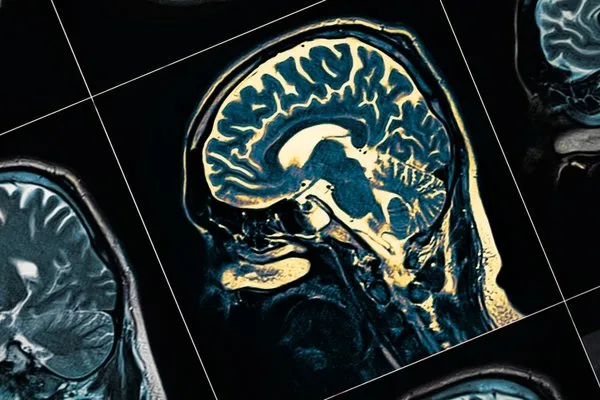

Yaş, genetik yatkınlık ve down sendromu gibi değiştirilemeyen faktörlerin yanı sıra, yaşam tarzı, alkol tüketimi, kardiyovasküler hastalıklar, işitme-görme kaybı, depresyon, hava kirliliği ve uyku bozuklukları gibi değiştirilebilir riskler de demans gelişiminde etkili olabiliyor.

Dünya Sağlık Örgütüne (DSÖ) göre, günümüzde dünya genelinde 55 milyondan fazla insan demans hastalığıyla mücadele ediyor, her yıl yaklaşık 10 milyon yeni demans vakası görülüyor.